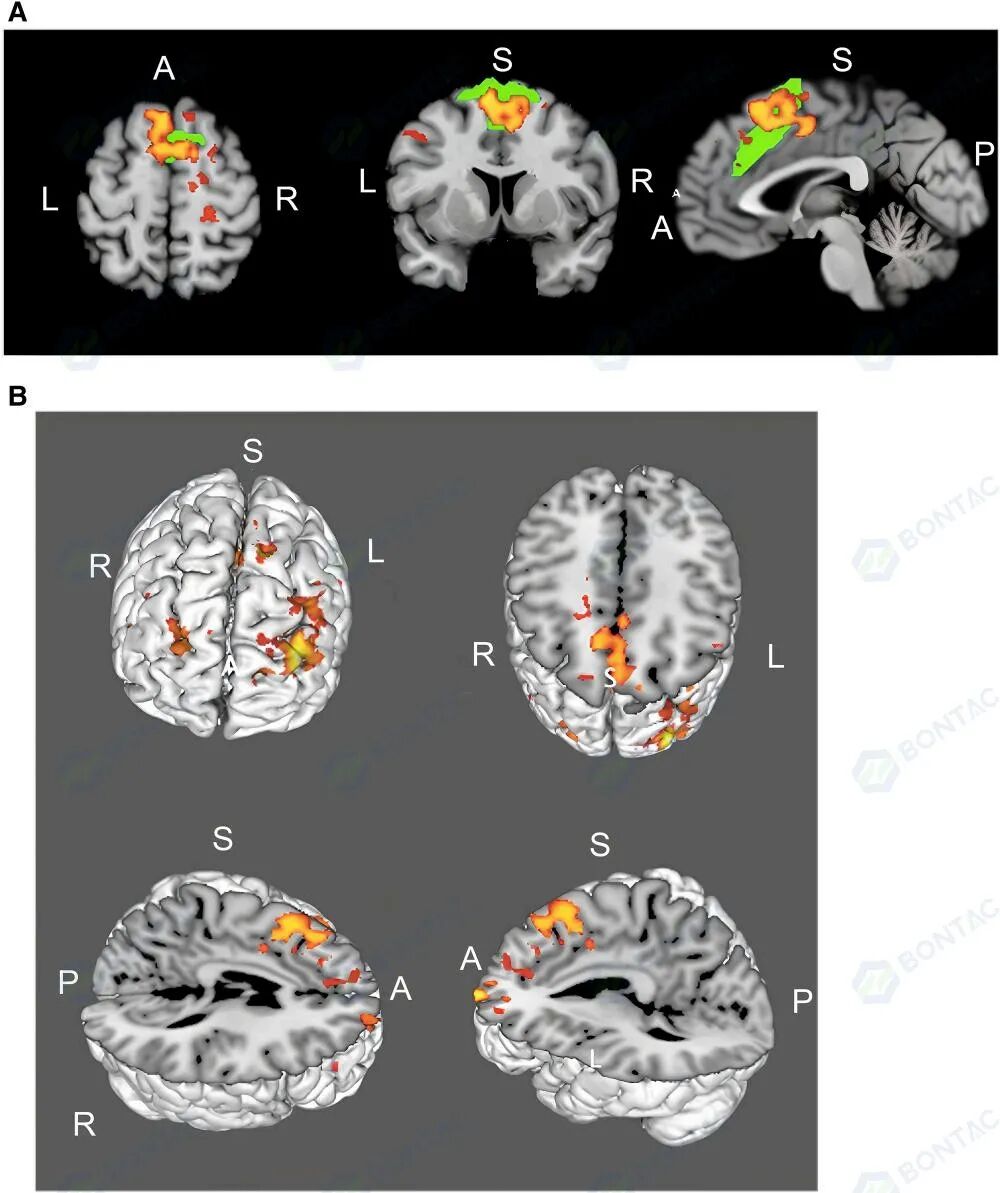

脑网络层面:

• 功能MRI显示显著性网络活动增强(P<0.05)

• 涉及双侧额极、左副扣带回、左中额叶 gyrus、左辅助运动皮层、双侧上额叶 gyrus 及右中央前 gyrus 等关键认知区域,为认知改善提供了影像学支持